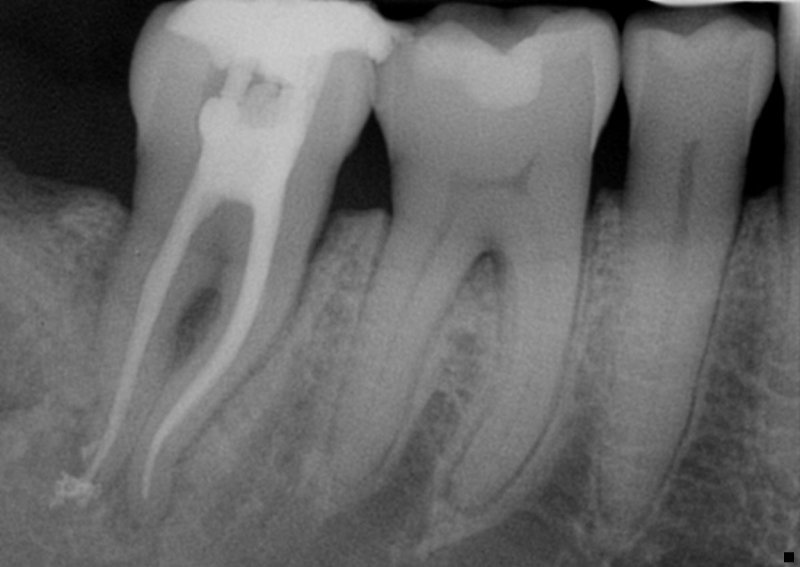

This is known as “fracture necrosis.” Figures 1A-1C highlight an undiagnosed root fracture in the lower second molar. Note non-vital pulp with periapical/periradicular bone loss and no restoration or caries. The clinician should question why the pulp became non-vital. With no other objective etiology, a vertical root fracture should be considered.

Radiographs and especially CBCT are valuable diagnostic tools for determining the presence of a root fracture. Unfortunately, unless the fracture is wider than about 0.15 mm (the tip of a #15 endodontic file), it cannot be visualized in the CBCT scan. There are some strong associations between radiographic findings and the presence of a root fracture. Specifically, when the bone loss presents in a “J” shaped pattern, it is highly suggestive that a root fracture is present.

This can often be seen on a two-dimensional periapical radiograph, with the bony lesion typically extending from the apex to the crestal bone, sometimes resulting in a deep and narrow isolated periodontal pocket. This pocket sometimes cannot be probed because it occurs in the interproximal area. Taking radiographs of the lower second molars can be challenging, especially with patient compliance (sometimes the tooth is “way back there” and may be uncomfortable for the patient).

Consider this: lower second molars are typically positioned in the cancellous bone, almost directly in the middle of the buccal and lingual cortical bony plates. When pulp necrosis becomes infected, the subsequent bone loss is only observed on a periapical radiograph when the bone loss reaches the junction of the cancellous and cortical bone. This makes the radiographic diagnosis of pulp necrosis difficult, especially for the lower second molar. CBCT can be essential in determining periapical or periradicular bone loss (see Figures 2A-2B).